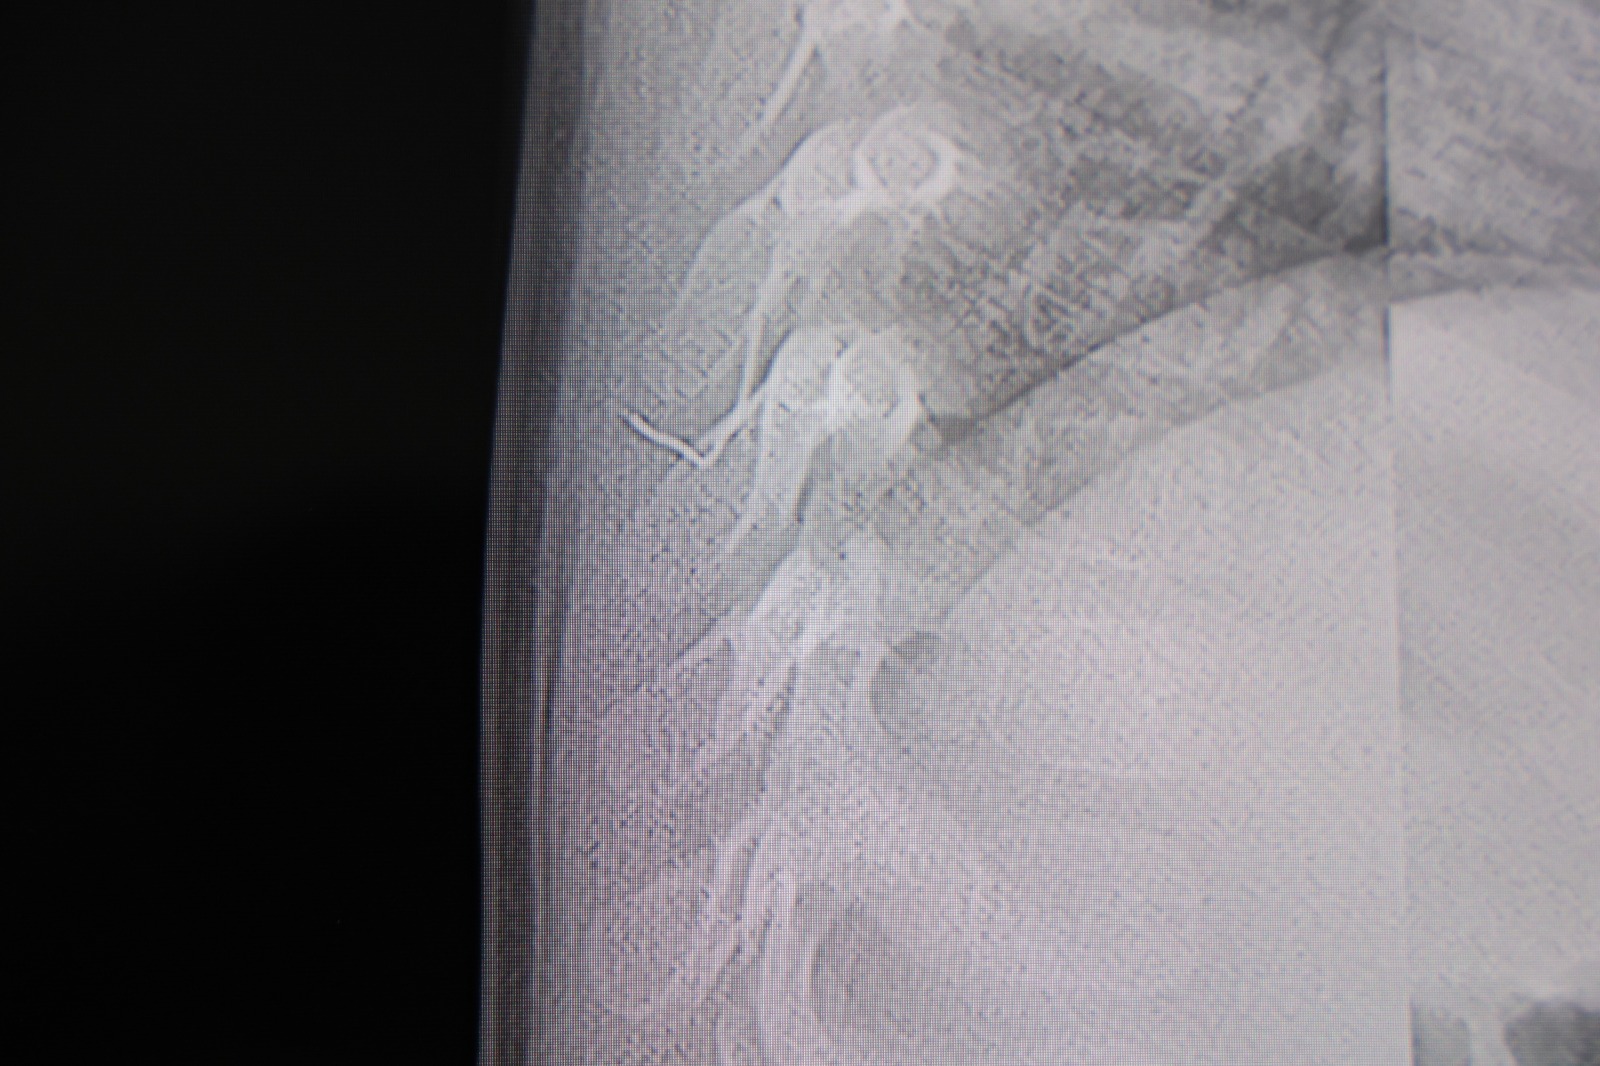

HG Hospital Beyin ve Sinir Cerrahisi Uzmanı Prof. Dr. İdris Altun tarafından yapılan tetkiklerde, yabancı cismin cilt altında, omurilik kanalına yakın bir bölgede olduğu ve akciğer zarına doğru ilerlediği belirlendi. Hasta, genel anesteziye alınmadan, lokal anestezi ve sedasyon eşliğinde ameliyata alındı. Yapılan müdahalede yabancı cisim tamamen çıkarıldı. Çıkarılan cismin, ince zımba teline benzer metal bir tel olduğu ve yaklaşık 2 santimetre uzunluğunda bulunduğu tespit edildi. Hasta, aynı gün taburcu edildi.

Hastamızı tamamen uyutmadan, lokal anestezi ve sedasyon eşliğinde müdahale ederek lezyonu tamamen çıkardık. Çıkardığımız cismin ince zımba teline benzer, yaklaşık 2 santimetre uzunluğunda metal bir tel olduğunu gördük. Bu yabancı cisim alınmasaydı, bölgede enfeksiyon gelişebilirdi.